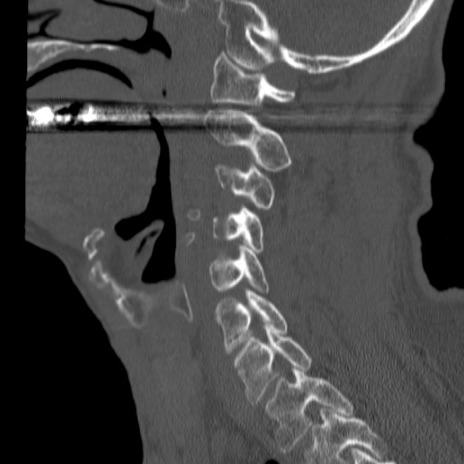

症例46 頚椎CT(矢状断像)

【症例】80歳代男性

【主訴】両側頚部〜上肢のしびれ

【現病歴】昨日、自宅内で転倒、その後より上記症状あり。意識障害なし。

【身体所見】両側上肢のallodynia(熱痛覚過敏)あり。MMTおよびDTRは正確な所見取れず。両上肢の挙上はなんとか可能。

異常所見と診断は?